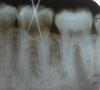

ANNA10 Опубликовано 4 июня, 2010 Поделиться Опубликовано 4 июня, 2010 (изменено) Добрый вечер!Попытаюсь описать все по порядку. В феврале, почти 4 мес назад у меня заболел зуб левая 6-ка снизу. Сделали снимок - сказали пульпит вот снимок это снимок во время лечения в первое посещениеэто снимок через 8 дней стоматолог сказал что все нормально ,только поболит 2-3 дня, и нужно поставить коронку И все это время у меня болит зуб на мои жалобы врач говорил что так и должно быть , скоро пройдетчерез месяц я сделала снимок мне сказали ждать и терпеть так как каналы запломбиоованы хорошо,а вскрывать жалко.Две недели назад распухла десна,сильная боль при малейшем надавливании на зуб врач вскрыл зуб и сказал что нашел причину поставил метапекс и мне придти через месяц ставить постоянную пломбу (если не будет болеть) Вот снимок Изменено 4 июня, 2010 пользователем ANNA10 Ссылка на комментарий

Снежана Опубликовано 4 июня, 2010 Поделиться Опубликовано 4 июня, 2010 а сколько каналов пломбировали?по снимкам похоже, что два, возможно не все каналы обработали. Ссылка на комментарий